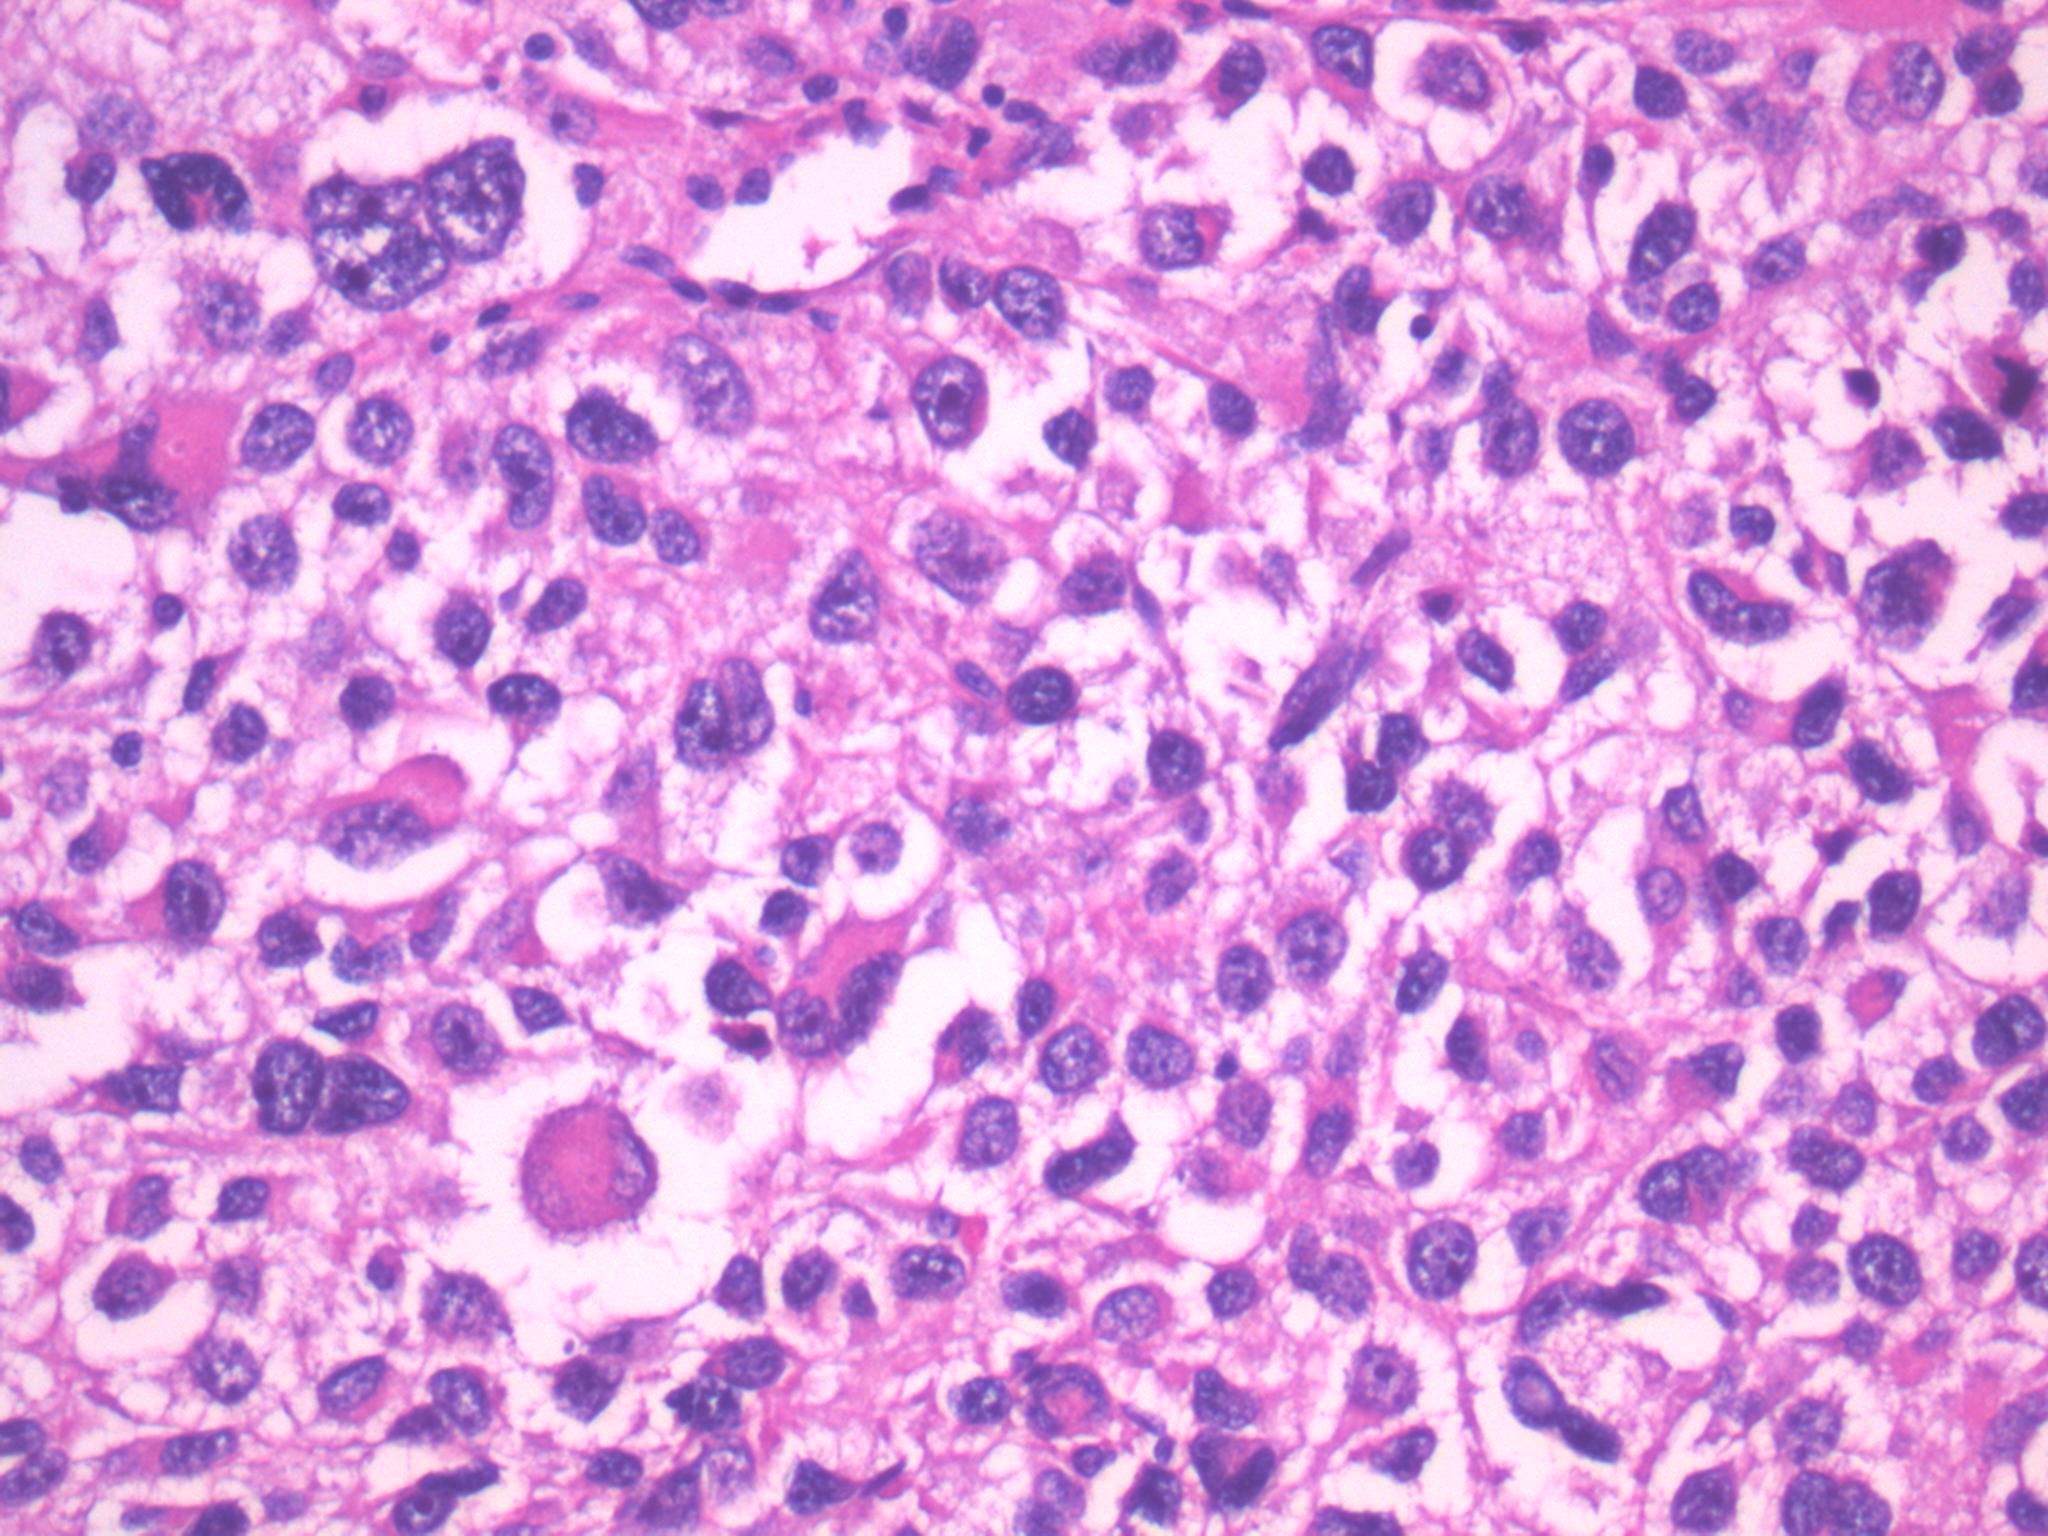

Renal tumor grading

Case ID: 1076